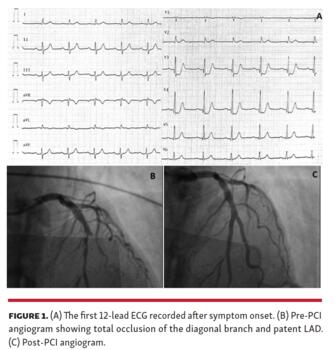

A 70-year-old man without previous cardiologic history was referred to the emergency department for an episode of ongoing chest pain during physical activity. The first electrocardiogram (ECG) showed downsloping ST-segment depression at the J-point and tall, symmetric T-waves in leads V3-V4 (Figure 1A). The first troponin I (TnI) determination was 0.18 ng/mL (normal value, <0.04 ng/mL); potassium levels on admission were completely normal. The patient underwent urgent coronary angiogram, which revealed a 75% stenosis in the left anterior descending (LAD) coronary artery and a total occlusion of a large diagonal branch (Figure 1B). Both stenoses were treated successfully with percutaneous coronary intervention (Figure 1C). Echocardiography revealed anterior free wall, septum, and apex akinesia. After reperfusion, the ECG developed negative T-waves in V2 through V6, DI, and aVL. The ECG pattern presented in this case, described in the literature as a “De Winter” pattern, is a possible manifestation of an acute anterior myocardial infarction due to LAD occlusion, with a reported incidence of 2%.

The De Winter pattern should be promptly recognized and lead to the same approach (such as immediate coronary angiography) of an anterior ST-segment elevation pattern. In this case, which is the first described in the literature to the best of our knowledge, the pattern was the ECG expression of a culprit lesion located in a large diagonal branch rather than in the LAD.